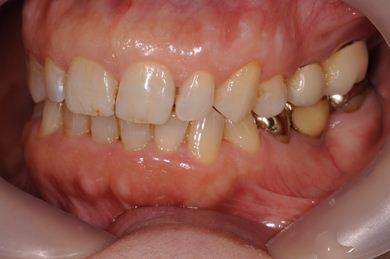

| 性別/年齢 | 女性 / 59歳 | ||||||||||||||||||||||||||||||||

| 主訴 | 奥歯がないので、インプラントか入れ歯の相談をしたい。 | ||||||||||||||||||||||||||||||||

| 治療方針 | 左上奥ソケットリフトにて上顎洞を拳上、骨再生法を行い、インプラント治療を可能にする。 | ||||||||||||||||||||||||||||||||

| 治療内容 | インプラント4本(GBR)、ハイブリッドセラミック4本 | ||||||||||||||||||||||||||||||||